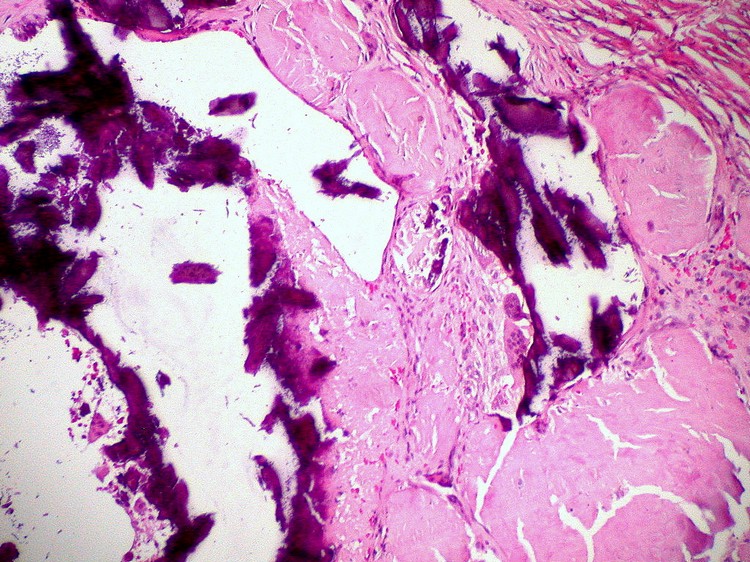

- Distrofik Kalsifikasyon

1- Distrofik kalsifikasyon; diğer bir tanımla Postdistrofik kalsifikasyon; insan dokusunda oluşan doku ölümü sonucunda dokunun hasarlı bölgesinde kalsiyum tuzları depolanmaya başlanması (kireç tuzlarının birikmesine) ile bilinir. Distrofik kalsifikasyonda dokularda pH’nın düşmesi ya da fosfataz faaliyetinin artmış olması kalsiyum tuzlarının çökmesini sağlar/hızlandırır.

Distrofik Kalsifikasyon